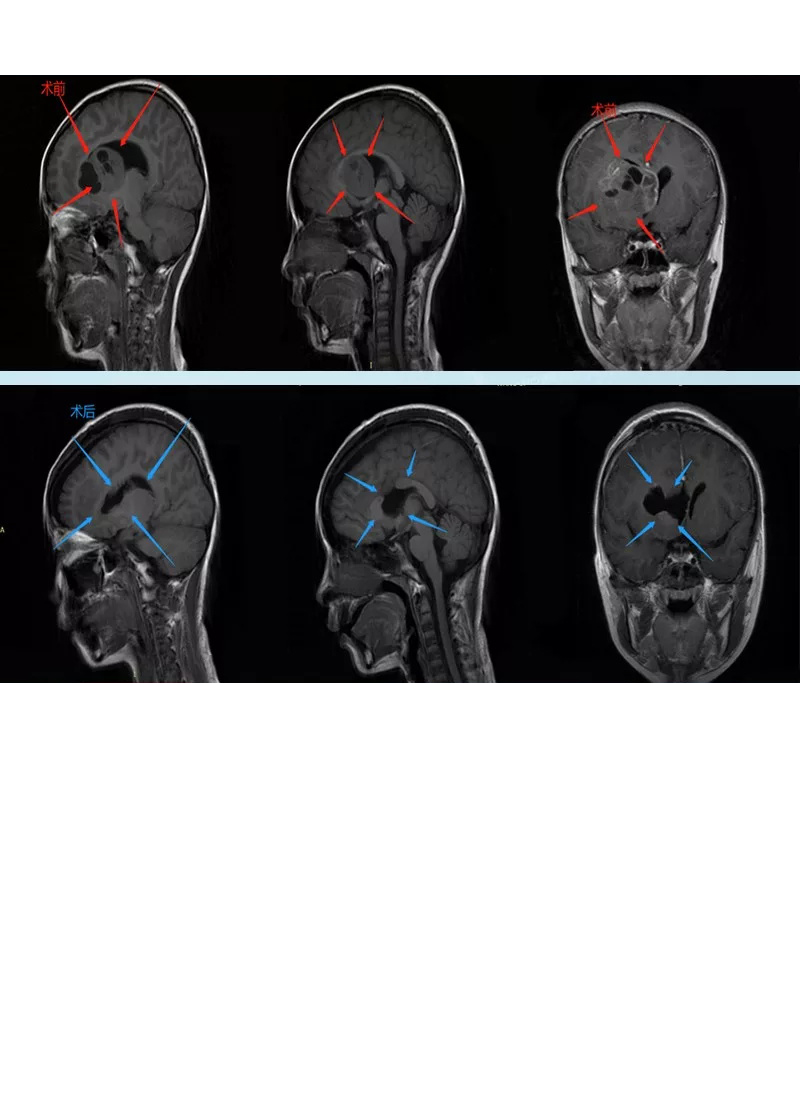

“头颅CT检查:左侧基底节区异常密度影,占位性病变伴出血?;头颅MRI:左侧基底节区异常信号,考虑不同感染性病变?肿瘤?。PET-CT示:左侧基底节高密度结节影,FET代谢异常增高,考虑肿瘤伴卒中可能大。”

8岁女孩小菲(化名)因头疼送医查出颅内基底节区肿瘤504137mm占位,病变区域靠近右侧管理运动功能的皮质脊髓束。鉴于脑深部肿瘤位置复杂,手术切除难度较大,很可能面临损伤颅内正常脑组织从而带来终身神经受损风险,很多医生在这个位置成功手术(不造成术后神经功能受损)的把握并不大。

INC巴教授主刀手术后

手术情况:如巴特朗菲教授所评估,肿瘤几乎完全切除,而且没有任何神经损伤,并且术后一周就可以正常地行走。